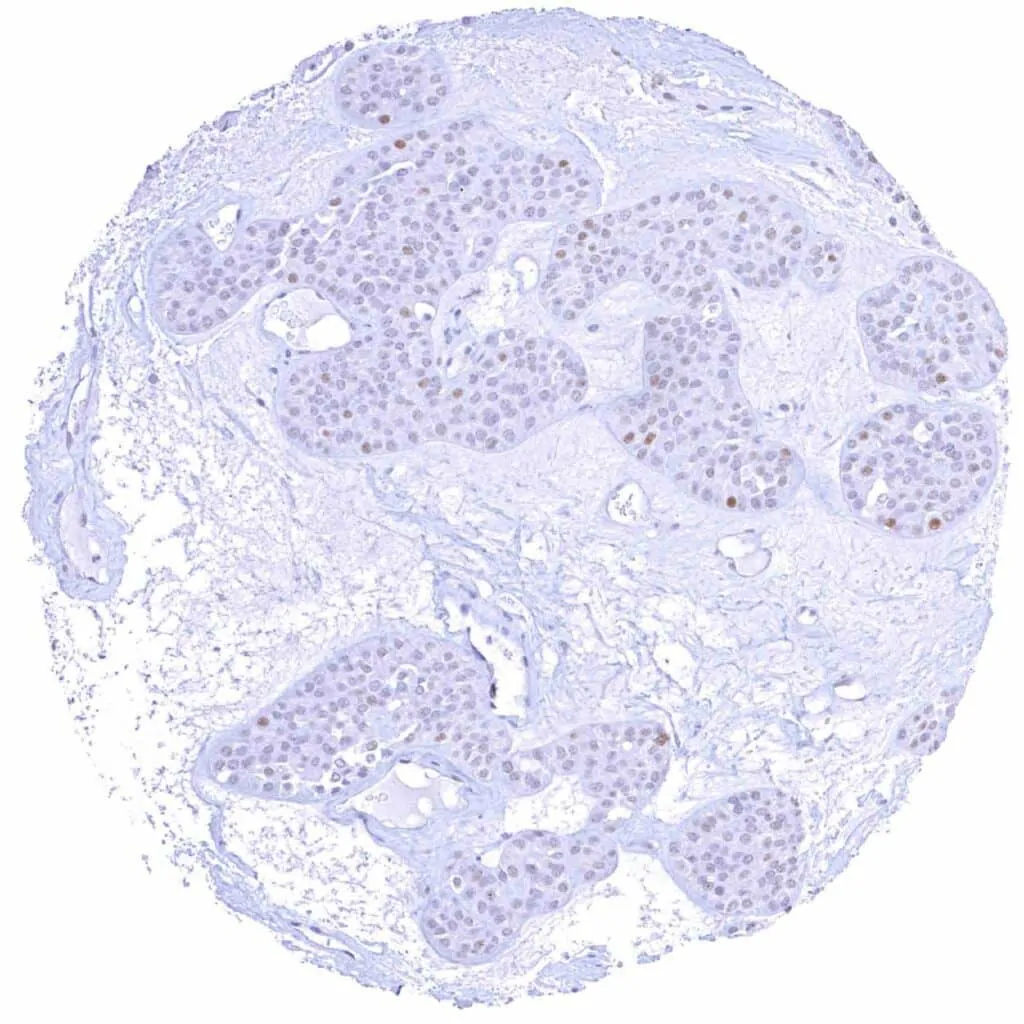

Urinary bladder – Non-invasive urothelial carcinoma (low grade, pTaG2) with a low to moderate Cyclin E1 staining of tumor cells